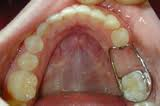

Space maintainers:

These are given to maintain the space for the permanent teeth in case of prematurely lost deciduous teeth.